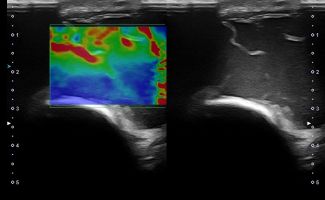

Elbow Ultrasound provides comprehensive imaging of various structures in the region, allowing the identification of pathologic conditions in the joint, bursae, tendons, ligaments, nerves, and soft tissues of the elbow.

Dynamic Testing: Ultrasound is inherently a dynamic imaging method, meaning that the examination and diagnosis can occur during movement. This capability is particularly important for Elbow Ultrasound, allowing a comprehensive examination of the area in various positions and movement points.